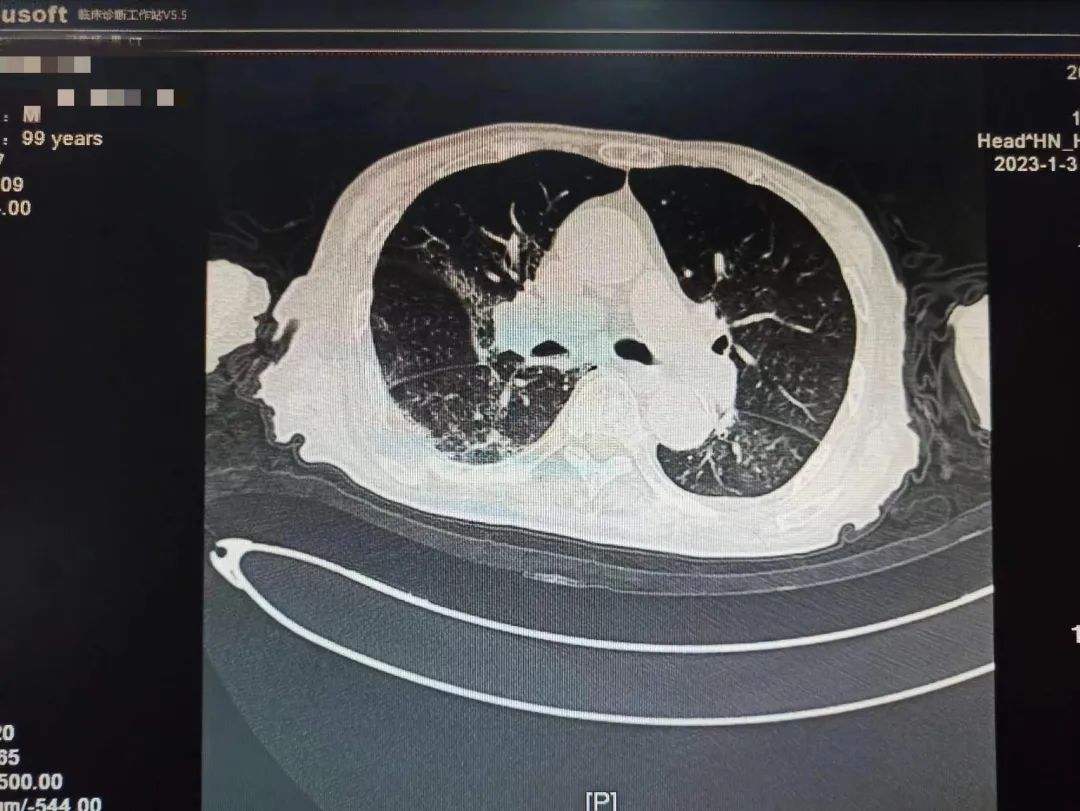

学校一附院呼吸与危重症医学科一名患者刘老爷子还差几天就到100岁生日,该患者从2022年12月22日开始持续发热,咳嗽。一开始只是以为普通的感冒,没特殊注意,后逐渐出现胸闷,乏力,精神差,在当地医院完善肺部CT,两肺大片病毒性肺炎表现,新冠核酸阳性,家属急送一附院就诊。

根据国家卫健委发布《新冠冠状病毒感染诊疗方案》最新版本指南及结合患者个体化诊疗,考虑到老人高龄,有糖尿病基础疾病,血氧饱和度偏低,属于危重症高危人群,专家团队决定给予paxlovid抗病毒治疗,激素、呼吸支持等治疗。患者住院期间一度出现嗜睡,精神极差,刘家昌主任团队时刻关注病情变化,随时调整治疗方案,并多次指出,对于这种重症肺炎患者治疗中,血氧饱和度偏低的情况,俯卧位通气具有非常重要的作用!需要“应趴尽趴”,对血氧饱和度偏低有明显改善作用!

不放弃每一个生命!全力救治!经过连续数日医护团队的精心救治,2023年1月9日,呼吸与危重症医学科医护团队再次对老人病情进行综合评估,检查显示患者肺部病灶明显吸收,精神明显好转,可以正常活动,和感染前身体体征一致。出院当天老人握着刘家昌主任的手激动的说:“多亏刘主任了,要不是你和咱们医院医护团队,我这关是闯不过去了,我还以为我过不去这一百岁坎了。”刘家昌主任对老人和家属详细交代了出院康复指导意见及注意事项。